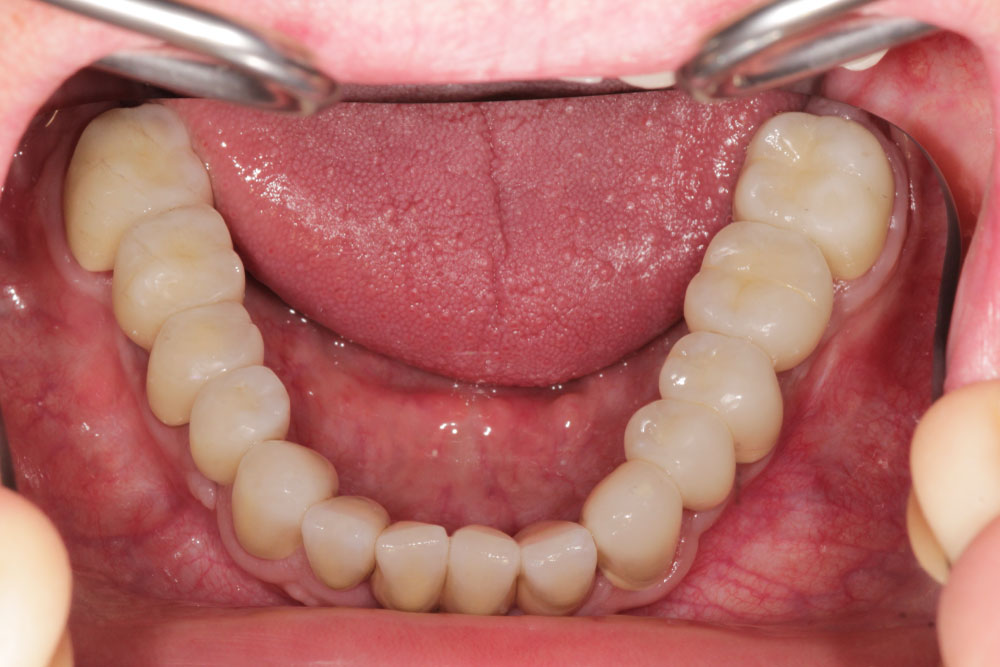

In November 2007, a male patient with ICD10 (K00.0; K07.1) asked for treatment. The diagnosis included craniomandibular malfunction, dysgnathia class III, maxillary retrognathia with horizontal and transverse narrowing of the maxilla, mandibular prognathia with lingual tipping of the mandibular front teeth (Figure 1). Additionally, we diagnosed multiple missing of permanent teeth and hypodontia of deciduous teeth with cones (Figure 2, Figure 3 and Figure 4). Systemically, the patient suffered from platelet deficiency and thrombocytopenia.

After 6 months of healing, the implants could be revealed and individual gingiva formers were incorporated to shape the soft tissue (Figure 11).After additional three months, the final prosthetic device of high esthetic standard could be incorporated: Circonia for the maxilla and SiO2 ceramics for the mandible (Figure 12, Figure 13, Figure 14 and Figure 15).

Figure 14: Intraoral mandibular dental restoration with single crowns on natural teeth and implants. View Figure 14

Figure 15: Orthopantomography at the end of treatment. Implant 14 not charged. View Figure 15